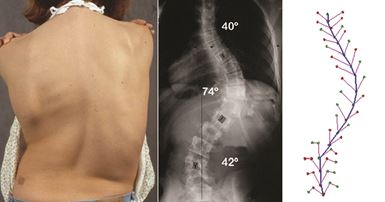

3D Ultrasound Imaging for Spine Scoliosis